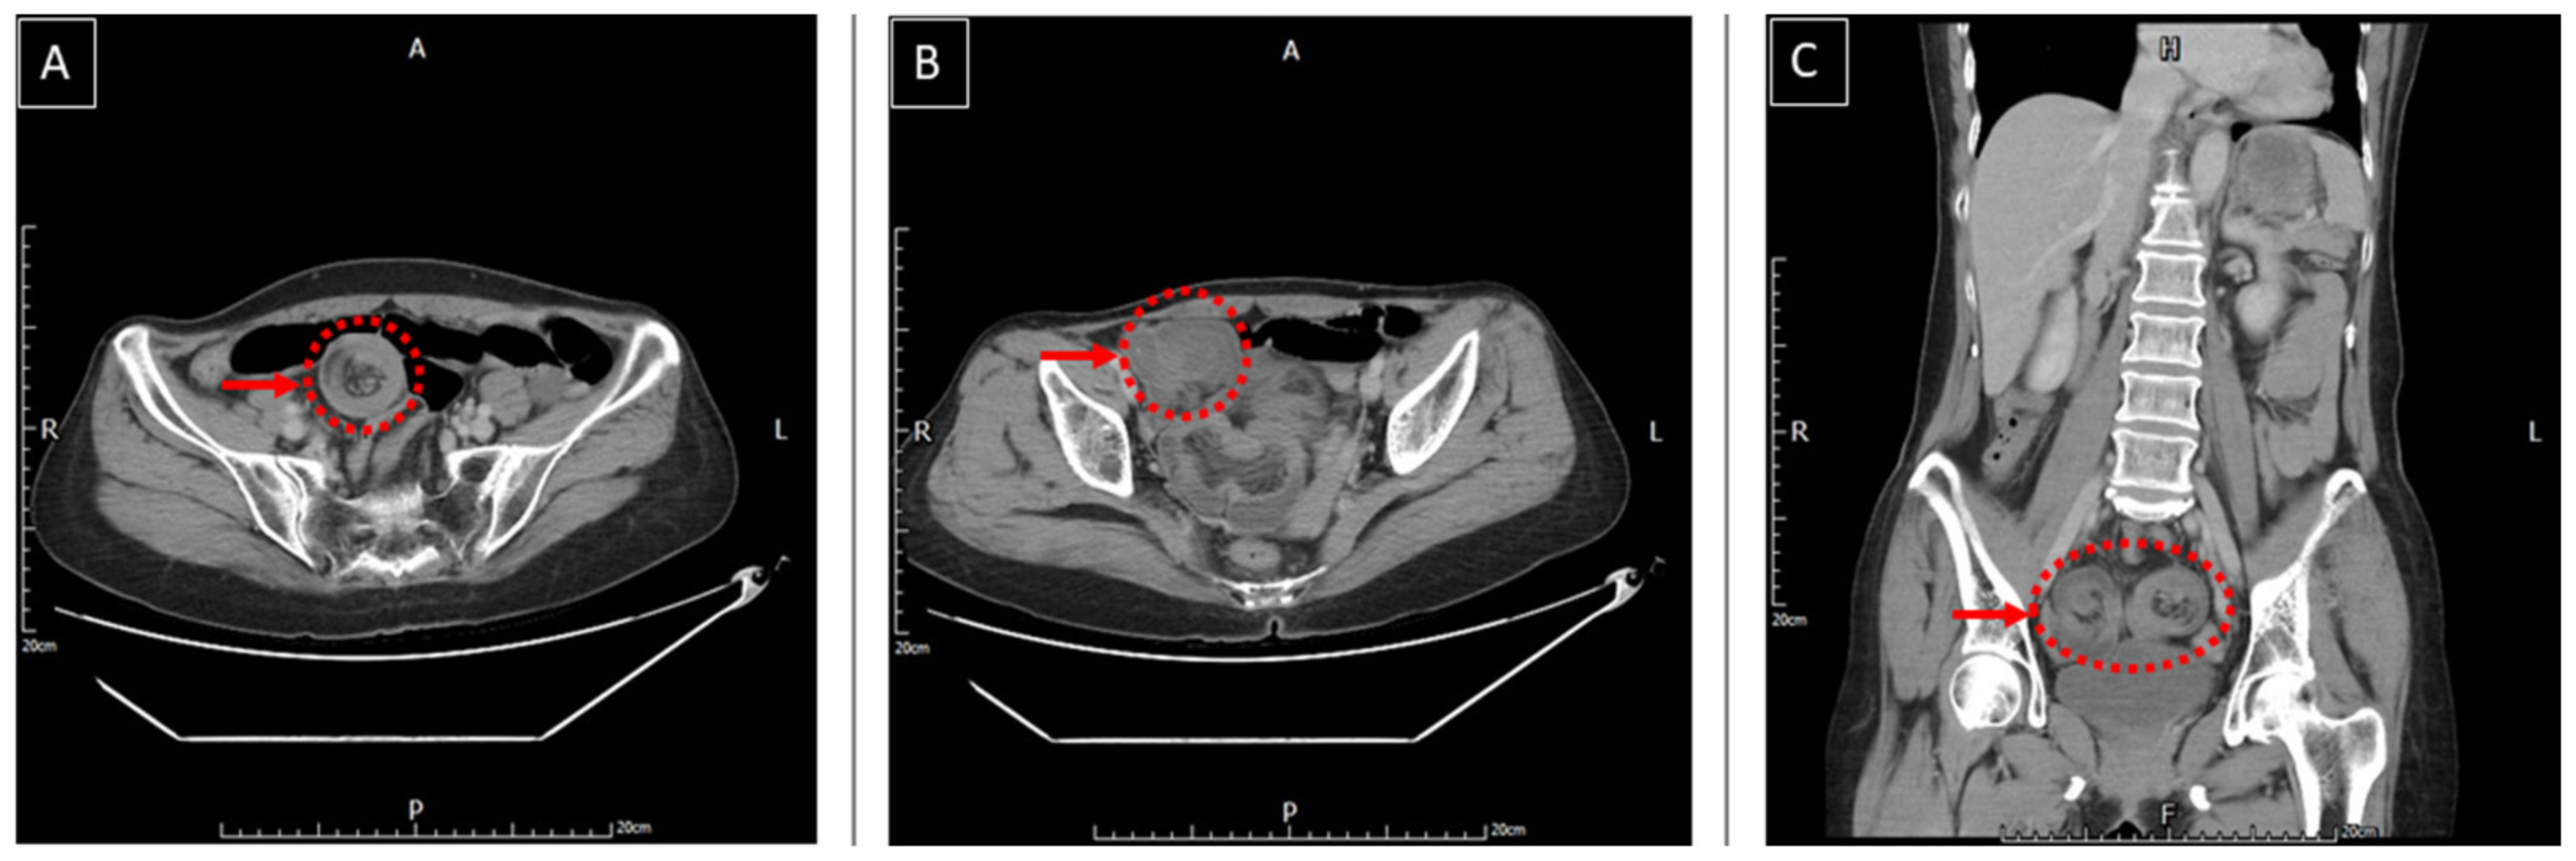

2. Case Report